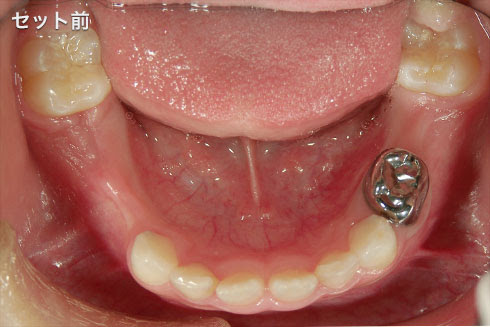

ひどい虫歯の治療例 22歳 女性 荻窪 歯医者 歯科 まうな歯科医院 荻窪駅南口 徒歩 1分